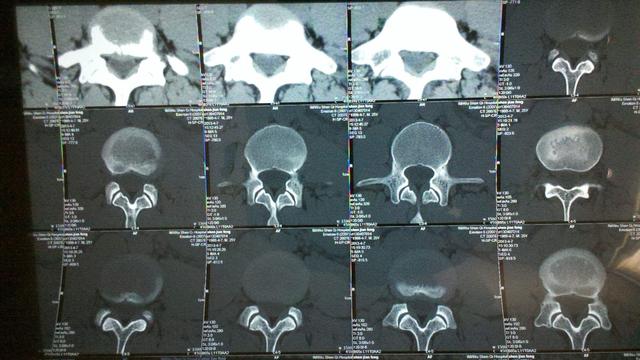

现在差不多弄明白了,阿姨现在很可能就是腰椎间盘突出症。就是因为这个疾病的缘故,两个月都特别难受,但是进一步检查还是要做腰椎CT,毕竟我们所考虑的都是猜测,讲事情还是要拿事实出来说话。

立即给阿姨约了一个腰椎CT,很快就排上了,结果拿回来一看,果真就是腰椎间盘突出症。可以在CT上看到明显的腰椎间盘突出以及局部的钙化压迫到了神经根,导致了现在的症状。